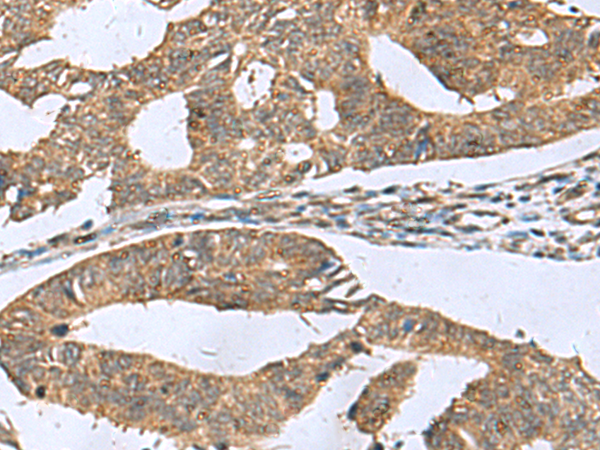

IHC positive control: |

Human liver cancer and Human colorectal cancer |